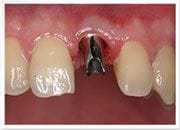

植牙過程

治療前